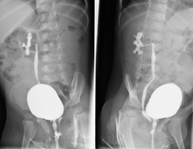

La urografía intravenosa (U.I.V.) consiste en la obtención de imágenes radiológicas seriadas del riñón, de las vías urinarias y la vejiga. Este estudio requiere, siempre, del empleo de un contraste yodado. - Cistografía (CUMS)

La cistouretrografía miccional seriada consiste en la obtención de imágenes radiológicas para valorar la anatomía y la función de la uretra y la vejiga con la administración de contraste yodado a través de una sonda vesical. - Uretrocistografía (Uretro-Cums)

La uretrocistrografía retrógrada y miccional consiste en la obtención de imágenes radiológicas para valorar la anatomía y la función de la vejiga y de la uretra. Se aplica material de contraste a través de una pequeña sonda alojada en la uretra y se obtienen imágenes durante el llenado y vaciado de la vejiga. - Pielografía ascendente por catéter